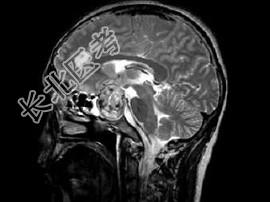

- 单项选择题男,26岁, 突发性视力障碍3天,根据所提供图像, 最可能的诊断为 ( )

D、嫌色细胞瘤(垂体瘤卒中)